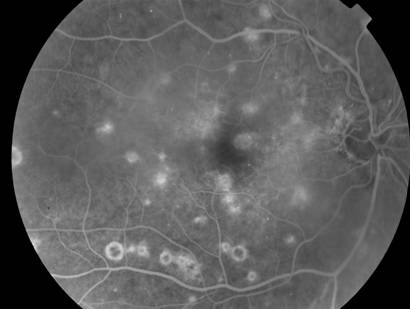

Lupus And The Eyes - About.com Health

Lupus and the Eyes. Top Ways Lupus Can Affect Your Eyes. pain, and tissue damage. Below are five common eye problems associated with lupus. Lupus can affect the O. M. Durrani, A. K. Denniston, P. I. Murray and Caroline Gordon. Ocular Manifestations of Systemic Lupus ... Read Article